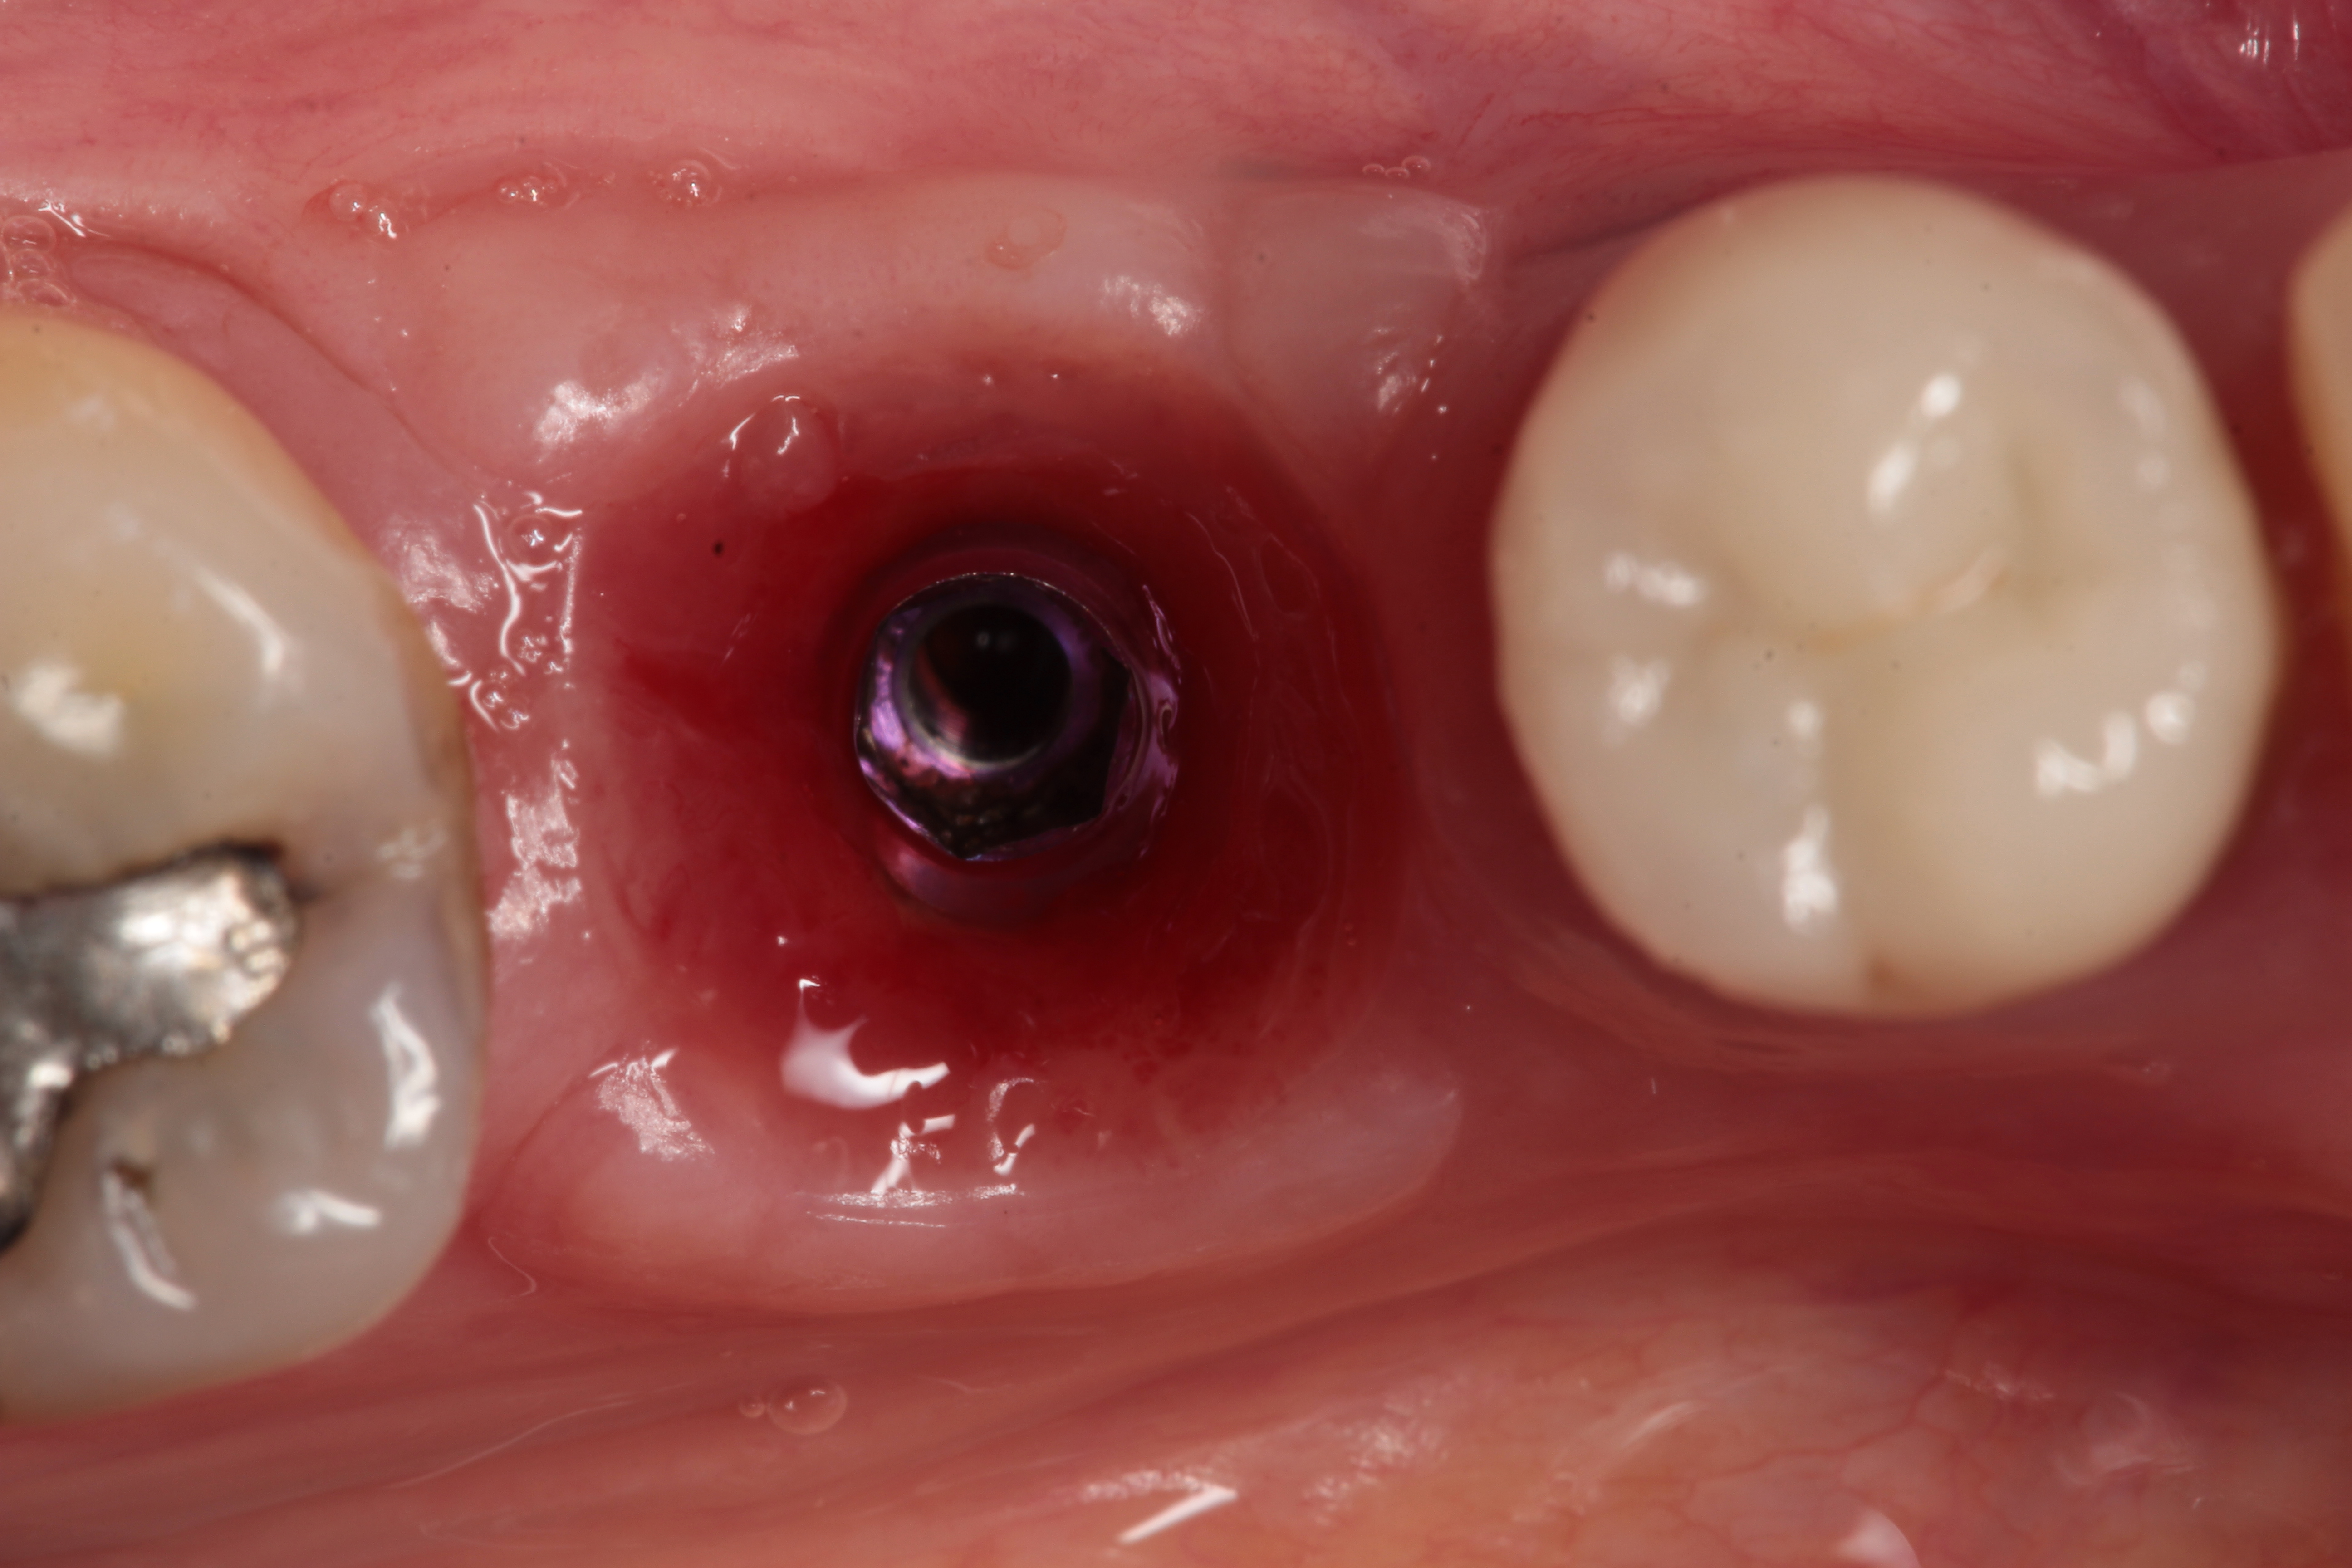

A 5 mm x 10 mm implant (MIS® V3, MIS Implants, mis-implants.com) had been placed at the mandibular first molar site and was ready for restoration. At the uncovering, a custom healing abutment that had been fabricated using an emergence profile management system (Cervico System, VP Innovato Holdings Ltd, vpicervico.com) to match the emergence profile of a mandibular molar was inserted into the integrated implant, and the soft tissue was sutured around the abutment (Figure 8). After several weeks to allow the soft tissue to heal, the restoration phase began. The custom healing abutment was removed, revealing healthy soft tissue with an emergence cross-section that was relatively square, mimicking a molar (Figure 9).

Fig 8. A custom healing abutment was created to replicate the emergence profile for a mandibular molar, which is square in cross-section.

Figure 8

Fig 9. After removal of the custom healing abutment, a natural-appearing emergence profile for a mandibular molar, square in cross-section, was evident.

Figure 9